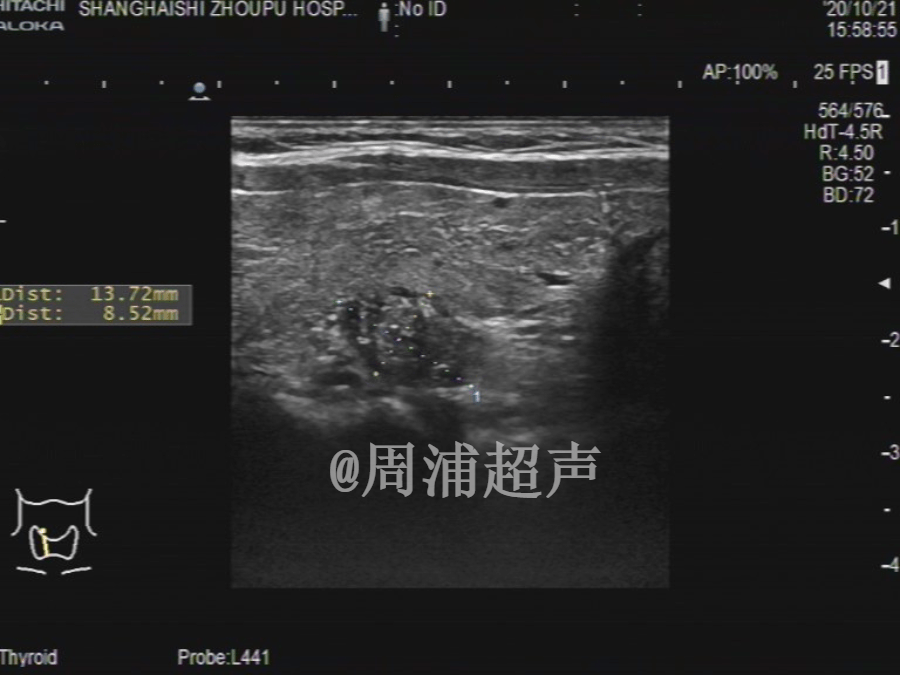

甲状腺超声报告 #甲状腺结节 #医学科普

图片尺寸576x1024